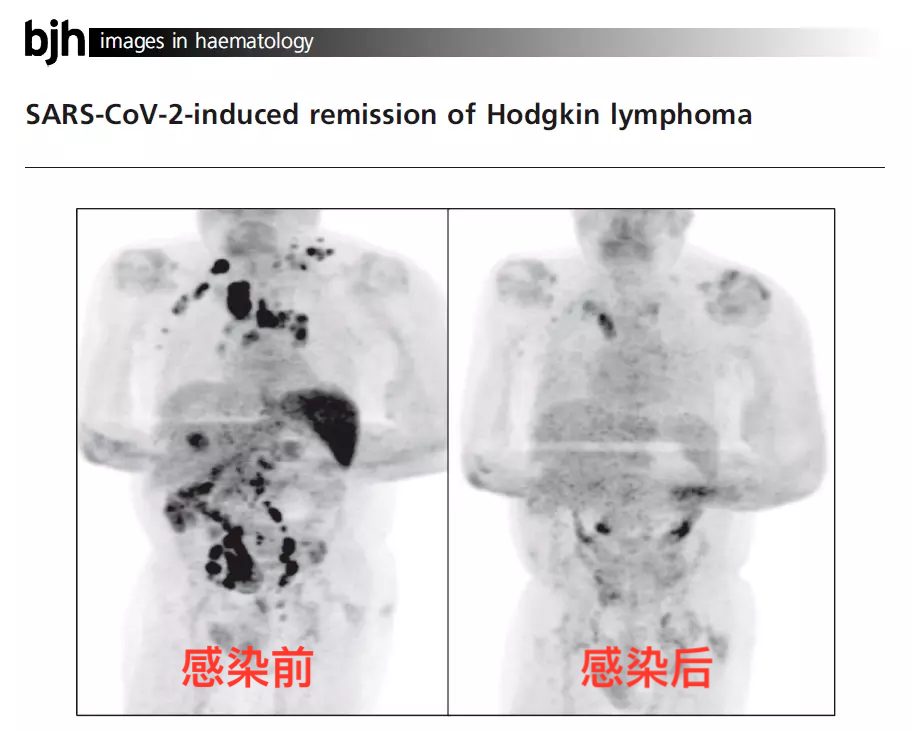

其次,人体最高的耐受热约为40.6~41.4摄氏度。如果发烧达到42摄氏度(家庭常用的体温计上限是42摄氏度,因为一般的发烧很难达到这个温度,即使达到了,人体大脑和内脏也很难承受超过42℃的高烧),即便高烧持续时间很短,也极有可能会导致永久性脑损伤、发生心肺功能衰竭,并有死亡风险[2]。总的来说,用发烧的方法来“杀死”癌细胞是不可行的!严重高烧可是会马上危胁生命的,而肿瘤是慢性病,并不会马上致命,结果可能是——肿瘤细胞没死,人也消耗得差不多了。又有患者疑问:“发烧不能杀死肿瘤,但我听说感染新冠后让肿瘤消失,这是真的吗?”当听到新冠会让肿瘤消失这件事,科普君的第一反应和大家一样:不相信,肯定是谣言。但事实上,感染新冠后,肿瘤奇迹“消失”还真有真实的临床案例,不是谣言。案例1:霍奇金淋巴瘤患者感染新冠病毒后,体内肿瘤几乎消失殆尽![3]2021年1月2日《英国血液病杂志》报道了一则医学奇迹:一名被诊断为霍奇金淋巴瘤、同时还患有严重肾功能衰竭、感染了EBV病毒的患者,被确诊感染了新冠病毒后,经过治疗,患者的新冠抗体转阴性后出院回到家中修养。这期间他没有用任何药物进行抗肿瘤治疗,但神奇的事,四个月后这名患者去医院做癌症常规检查时却发现,其体内大部分肿瘤竟神奇消失了。左边的图像中的黑色区域显示患者体内各处还散布着可怕的癌细胞;右边图像则显示肿瘤几乎完全消失案例2:纤维结缔组织瘤患者感染新冠后,胸部肿瘤奇迹消失[4]一位患者有艾滋病,同时还被断为纤维结缔组织瘤的患者,原本计划手术切除肿瘤,但手术前他感染了新冠病毒,不得不推迟手术,并使用对乙酰氨基酚和甲泼尼龙对症治疗。1个月后,医生通过触诊和CT检查却发现,患者胸部原有的肿块消失了!居然有这种好事!不是说癌症患者感染新冠会更危险吗?如果感染新冠病毒真能杀死癌细胞,让肿瘤消失,是不是可以主动感染新冠,那样说不定肿瘤消失这种好事就能降临降到自己身上呢。某些癌症患者感染新冠后肿瘤“不治而愈”,很可能是患者的免疫系统被再次“激活”,在对付新冠病毒的同时,“杀疯”了的免疫系统连体内的肿瘤细胞也顺手给灭了,算是一个偶然的意外收获,但这种情况可遇不可求。肿瘤患者普遍免疫力较低,部分患者还患有基础病,因此感染新冠后转重症的风险也会高于普通人。如果感染后不积极处理,后果可能会非常严重。例如,对于放化疗、靶向治疗期间的患者,由于这些治疗手段会抑制免疫,免疫清除能力低,感染新冠后可能会引起继发感染,癌细胞也更容易繁殖和扩散,有可能导致重症的发生。即使是已经处于康复期的患者,如果听信了“感染新冠能抗癌”,而不及时接受对症治疗,无疑给了癌细胞壮大的机会,导致癌细胞有机会不断地发展壮大,最终变成癌细胞转移扩散[5]。总而言之,个别肿瘤患者感染新冠后癌细胞奇迹消退,这是极低概率的事,并不是每个人都拥有这种“超能力”。因此,不建议肿瘤患者为了抗癌,而故意去感染新冠病毒。无论是“感染新冠病毒后发高烧可以消灭癌细胞”,还是“感染新冠病毒可以让肿瘤消失”,在这里互助君再次提醒:发烧不能烧死癌细胞,“阳了”建议要及时退烧。目前得新冠能不能让肿瘤消失还有待考证,个别肿瘤患者感染新冠后肿瘤神奇好转只是特殊个案!万不可仿效!感染新冠,肿瘤患者重症率和死亡风险都比一般人高,所以更应该:严格做好个人防护,尽力避免感染新冠。一旦感染新冠病毒后更应该:及时对症治疗,不要心存侥幸。对于不幸“阳了”的肿瘤患者,不要慌,根据国内数据结果发现,约80%新冠肺炎患者表现为轻症(轻型、普通型),预后良好[6]。因此感染后建议先判断一下自己是轻症还是重症。轻症:发热、咳嗽、咽喉痛、头痛、味觉及嗅觉丧失,但无明显气短、呼吸困难或胸部影像学异常。一般建议居家对症处理,多休息,适度多饮水。必要时(有发烧情况)咨询主治医生,在医生的指导下服用治疗药物。重症:持续发烧3天以上,而且出现心率增快、咳嗽咳痰加重、呼吸困难、口唇发干等表现,不要犹豫,立即就医。根据《美国国家癌症综合网络(NCCN)癌症相关感染的预防和治疗指南2022.3版》建议:新冠病毒检测阳性的肿瘤患者,建议推迟抗肿瘤治疗。